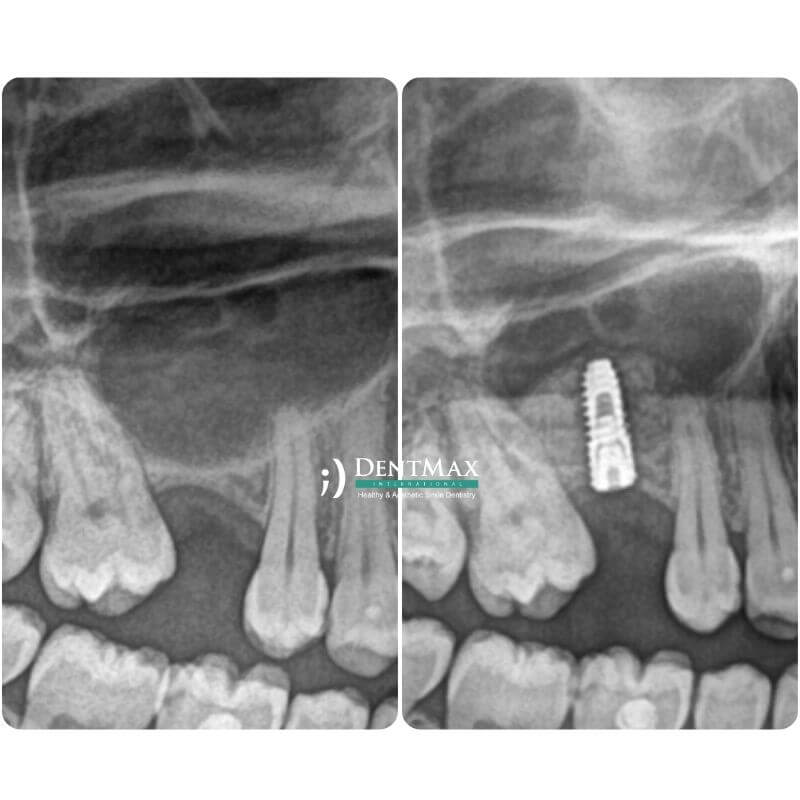

Костная пластика (Костная пудра)